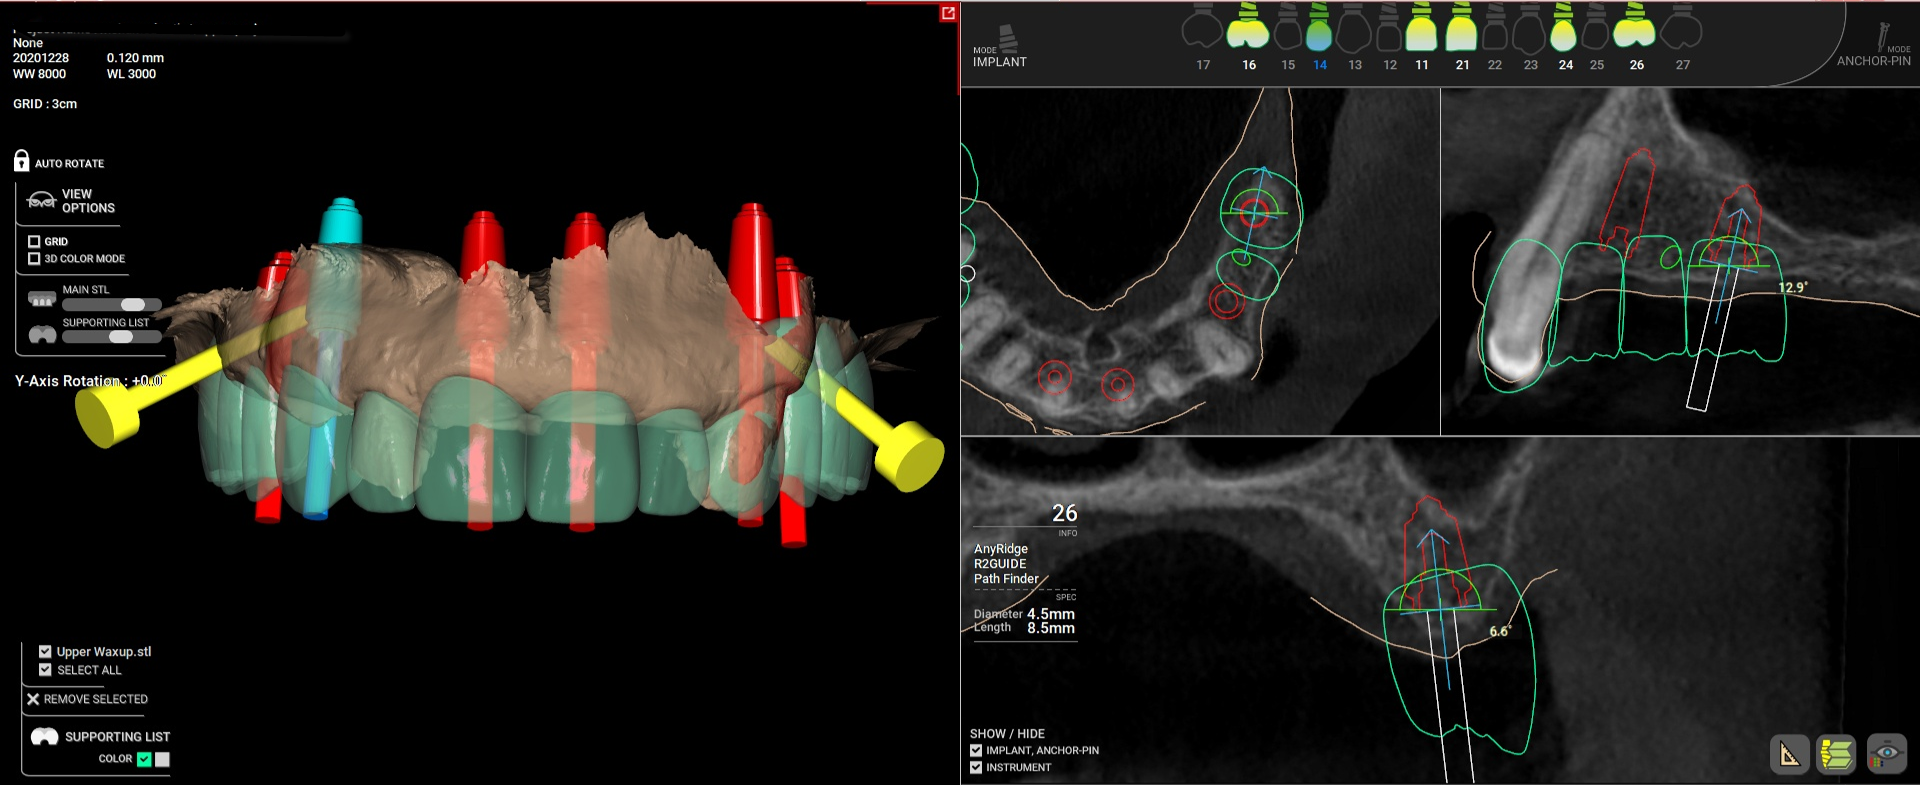

Digitālajai zobārstniecībai attīstoties un līdz ar jaunu digitālo rīku parādīšanos un izmantošanu, mēs ietaupīsim dārgo laiku, uzlabosim darbplūsmu un padarīsim pacientus laimīgākus.

“Padarīt labu zobārstniecību vēl labāku: Jaunas digitālas iespējas” uzzināsiet, kā efektīvāk rīkoties ar digitālajiem risinājumiem.

Sam Omar ir internacionāls lektors no Ēģiptes. Viņam ir sava privātprakse Ēģiptē, Kairā – ONEDAY CLINIC, kurā viņš strādā kā vispārējs zobārsts un implantologs. Dr. Sam Omar ir lasījis lekcijas vairāk kā 20 valstīs par inovācijām digitālajā zobārstniecībā un darbu ar ķirurģiskajiem gidiem.

• Internacionāls lektors par digitālās implantoloģijas, vadītās ķirurģijas un 1-dienas implantu protokolu tēmām.